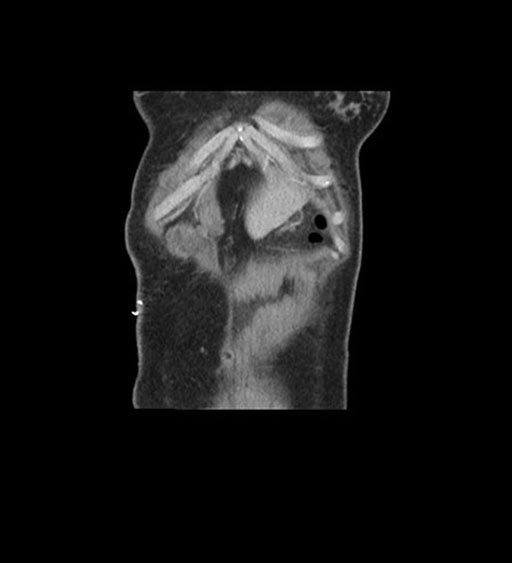

Coronal Arterial

Coronal Venous

Imaging analysis

Based on initial findings, which issue(s) would you be most concerned about?